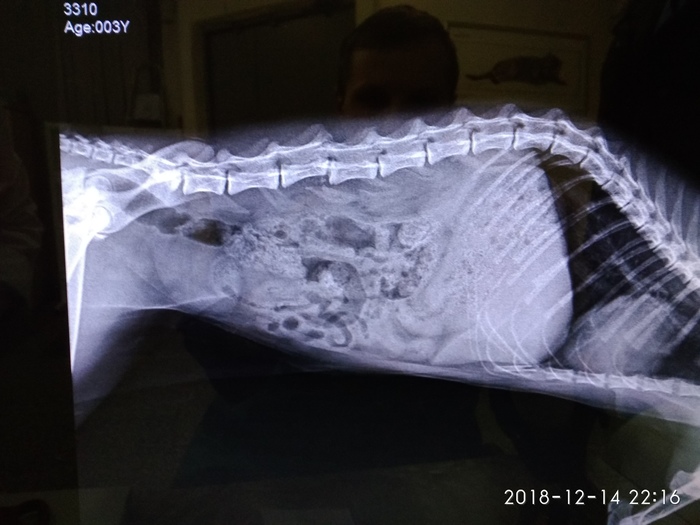

Этого кота зовут Сеня. Мы с друзьями его подобрали на трассе, в Санкт-Петербурге, когда все машины просто объезжали его в последний момент..Сеню кто-то сбил на большой скорости и теперь у него парализована вся нижняя половина туловища, включая задние лапки и хвост.

У Сени перелом позвоночника со смещением, кроме этого, он не может мочиться сам. Ветврач подарила нам катетер, с помощью которого нужно откачивать жидкость из мочевого пузыря примерно раз в сутки.Через каждые 48 часов, мы ставим ему уколы амоксициллина, назначенные ветеринаром, чтобы расслабить мышцы живота и, возможно, он сможет ходить в туалет сам, без помощи катетера.